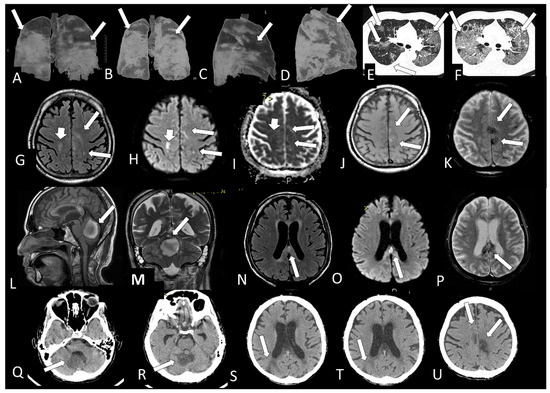

| 15 | M | 26 | seizure, hemiparesis | no | no | no | no | temporo-occipital hypersignal on FLAIR, hemosiderosis (MRI) | >50% | ICU | no | |

| 18 | M | 40 | yes | headache, hemiparesthesia, visual field fog | yes | yes | no | no | corpus callosum restricted DWI lesion and olfactory bulb injuries (MRI) | - | internal | no |

| 21 | M | 83 | - | lowering of level of consciousness | yes | yes | no | O2 catheter | signs of past frontal and cerebellar injuries (MRI) | 25–50% | ICU | no |

| 22 | M | 62 | - | severe depression, parkinsonism, coma | yes | no | yes | ventilator | olfactory bulb injury (MRI) | >50% | ICU | no |

| 24 | F | 25 | yes | headache | yes | no | no | no | olfactory bulb injury (MRI) | normal | external | no |

| 25 | F | 36 | - | headache | - | - | - | no | olfactory bulb injury (MRI) | normal | external | no |

| 26 | M | 71 | - | Neurologic sequel | - | - | - | no | parietal subcortical microbleeding (MRI) | >50% | ICU | no |

| 27 | F | 61 | - | headache | - | - | - | no | cortical/subcortical hematomas and pale globes microbleedings + olfactory bulb injury (MRI) | >50% | internal | no |

| 28 | M | 80 | - | seizure, recurrent syncope | yes | yes | yes | O2 catheter | frontal microbleeding and olfactory bulb injury (MRI) | <25% | ICU | no |

| 30 | F | 70 | - | yes | yes | yes | ventilator | microbleedings in base ganglia, brainstem and cerebellum (MRI) | >50% | ICU | yes | |

| 31 | M | 62 | - | coma | yes | yes | yes | ventilator | cerebellum, corpus callosum and parietal white matterbleeding and restricted DWI small lesions (MRI) | >50% | ICU | no |

| 32 | M | 40 | left facial palsy | yes | No | no | no | geniculate ganglion injury and olfactory bulb injury (MRI) | - | external | no | |

| 33 | M | 41 | encephalitis | - | - | - | - | olfactory bulb injury (MRI) | - | ICU | no | |

| 34 | F | 34 | stroke and seizure | - | - | - | - | old ischemic lesion with restricted DWI areas/right middle cerebral artery stenosis/areas of hemorrhage and olfactory bulb injury (MRI) | <25% | external | no | |

| 35 | M | 82 | desorientation | - | - | - | - | Small right parietal cortical gliosis (MRI) | >50% | internal | no |